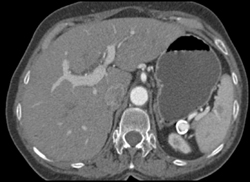

Splenic Artery Aneurysm